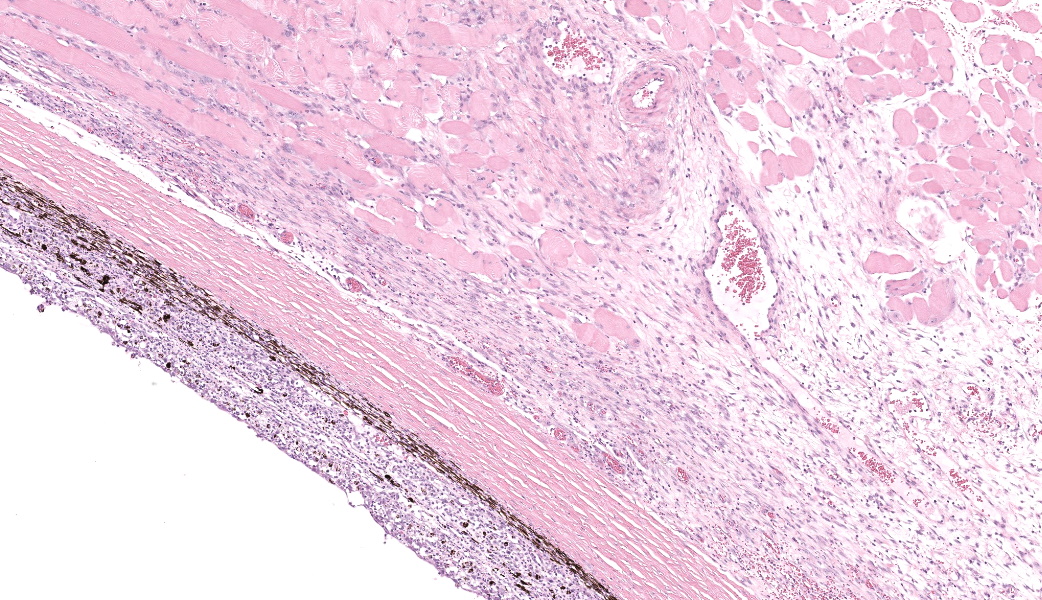

Filling all ocular chambers and coating the surfaces of intraocular structures are vast accumulations of exudate consisting of myriad degenerate and intact neutrophils, many macrophages, abundant amounts of fibrinous to proteinic material, abundant necrotic cellular debris, occasional pools of extravasated erythrocytes, and multifocal colonies of mixed bacteria (rods and coccobacilli). Centrally incorporated into the inflammatory exudates is a ruptured lens which lacks a capsule in many areas and has highly undulating free capsule margins regionally. The lenticular stroma is variably vacuolated with the following features: streaks of pallor, Morgagnian globules, many infiltrating leukocytes (mostly neutrophils), and occasional pockets of similar bacteria. The retina is diffusely detached and largely inapparent apart from remnant segments of atrophied and degenerate retina enmeshed within the exudate. Suppurative to pyogranulomatous inflammatory infiltrates multifocally extend into the iris, ciliary body, choroid, optic nerve which is significantly gliotic with rarefied neuropil, and optic nerve meninges. The iris is displaced anteriorly and multifocally abuts the posterior aspect of the cornea. The anterior chamber is severely narrow, and the drainage angle is collapsed and inapparent. The corneal stroma is moderately to markedly oedematous and contains small to moderate numbers of scattered neutrophils. The anterior corneal epithelium appears attenuated in areas. The sclera is variably thinned with multifocal often perivascular infiltrates of lymphocytes and plasma cells with variable numbers of admixed neutrophils and occasional macrophages. There are increased numbers of perilimbal pigmented cells. A thin to moderately thick layer of oedematous and inflamed granulation tissue regionally lines the mid and posterior scleral margins outside the globe and extends into a bundle of periocular skeletal muscle. In addition to infiltrates of the aforementioned inflammatory cells, the granulation tissue also contains many golden-brown pigmented macrophages (siderophages) which are concentrated at the level of the ciliary body. There is abundant haemorrhage in the retrobulbar loose connective tissue.Contributor's Morphologic Diagnoses:

Clinical findings in animals following orbital penetration during a dental procedure include vision loss, epiphora, mucopurulent ocular discharge, blepharospasm, exophthalmos, buphthalmos, glaucoma, hyphema, hypopyon, miosis, iris bombe, cataract, and orbital cellulitis. Gross examination of the globe commonly demonstrates opacification of the aqueous and vitreous humor and may reveal a site of scleral penetration. Histopathologic lesions include severe suppurative endophthalmitis or panophthalmitis, varying degrees of orbital cellulitis and episcleral fibrosis of the ventral aspect of the globe, and in some instances rupture of the posterior or equatorial lens capsule and/or presence of intraocular bacteria. Ventral scleral perforation may be appreciated in some cases, but a site of penetrating injury is not always detected. In this case, a scleral penetration site was not appreciated grossly or histologically despite review of multiple step sections.

Talk about a descriptive case that made, for obvious reasons, an excellent sales pitch on why pathology is the best profession! This case provides an excellent opportunity for participants to push themselves on their ocular descriptive abilities. Many thanks to this contributor for a fantastic case! Much like the previous eye case in this conference, there was substantial discussion on ocular pathology. The most informative nuggets from that conversation included utilizing the lens capsule, which is an easily identifiable structure in the eye, to assist with orientation in a busy ocular slide such as this one. The pigmented irideal stroma, as well as the “golden” fibers of the iris, can also be used to help identify structures that might otherwise be difficult to ascertain due to the degree of damage and/or inflammation.This case had beautiful examples of iris bombe (iris pushed forward into the anterior chamber and adhered to the back of the cornea), numerous types of fibrovascular membranes (retrocorneal, preiridial, cyclitic, etc.), and a fantastic phakoclastic panuveitis from lens rupture. The six types of uveitis and their definitions were discussed and included: 1) anterior uveitis (inflammation of the iris and ciliary body), 2) posterior uveitis (inflammation of the ciliary body and choroid), 3) panuveitis (iris, ciliary body, and choroid affected), 4) chorioretinitis (inflammation of the choroid and retina), 5) endophthalmitis (inflammation of uvea, retina, and ocular cavities), and 6) panophthalmitis (all ocular structures are affected, including sclera). Being able to recognize and accurately use these terms as pathologists can provide crucial information to ophthalmologists when it comes to treating these patients.